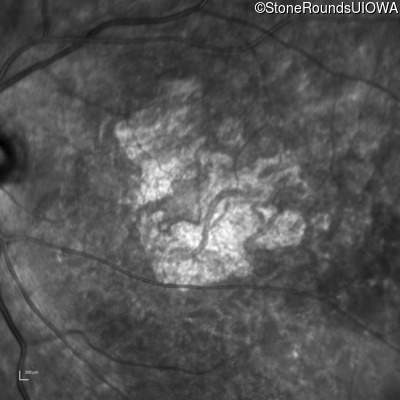

AR Stargardt Disease (IIA)

Age at visit: 61 years

This 61 year old woman first noticed an abnormality in the center of her vision in dim light when she was 8 years old.

Diagnosis & molecular findings

Disease Gene Allele 1 variant(s) Allele 2 variant(s) Inheritance mode

AR Stargardt Disease ABCA4 Pro1380Leu CCG>CTG IVS40+5 G>A AR